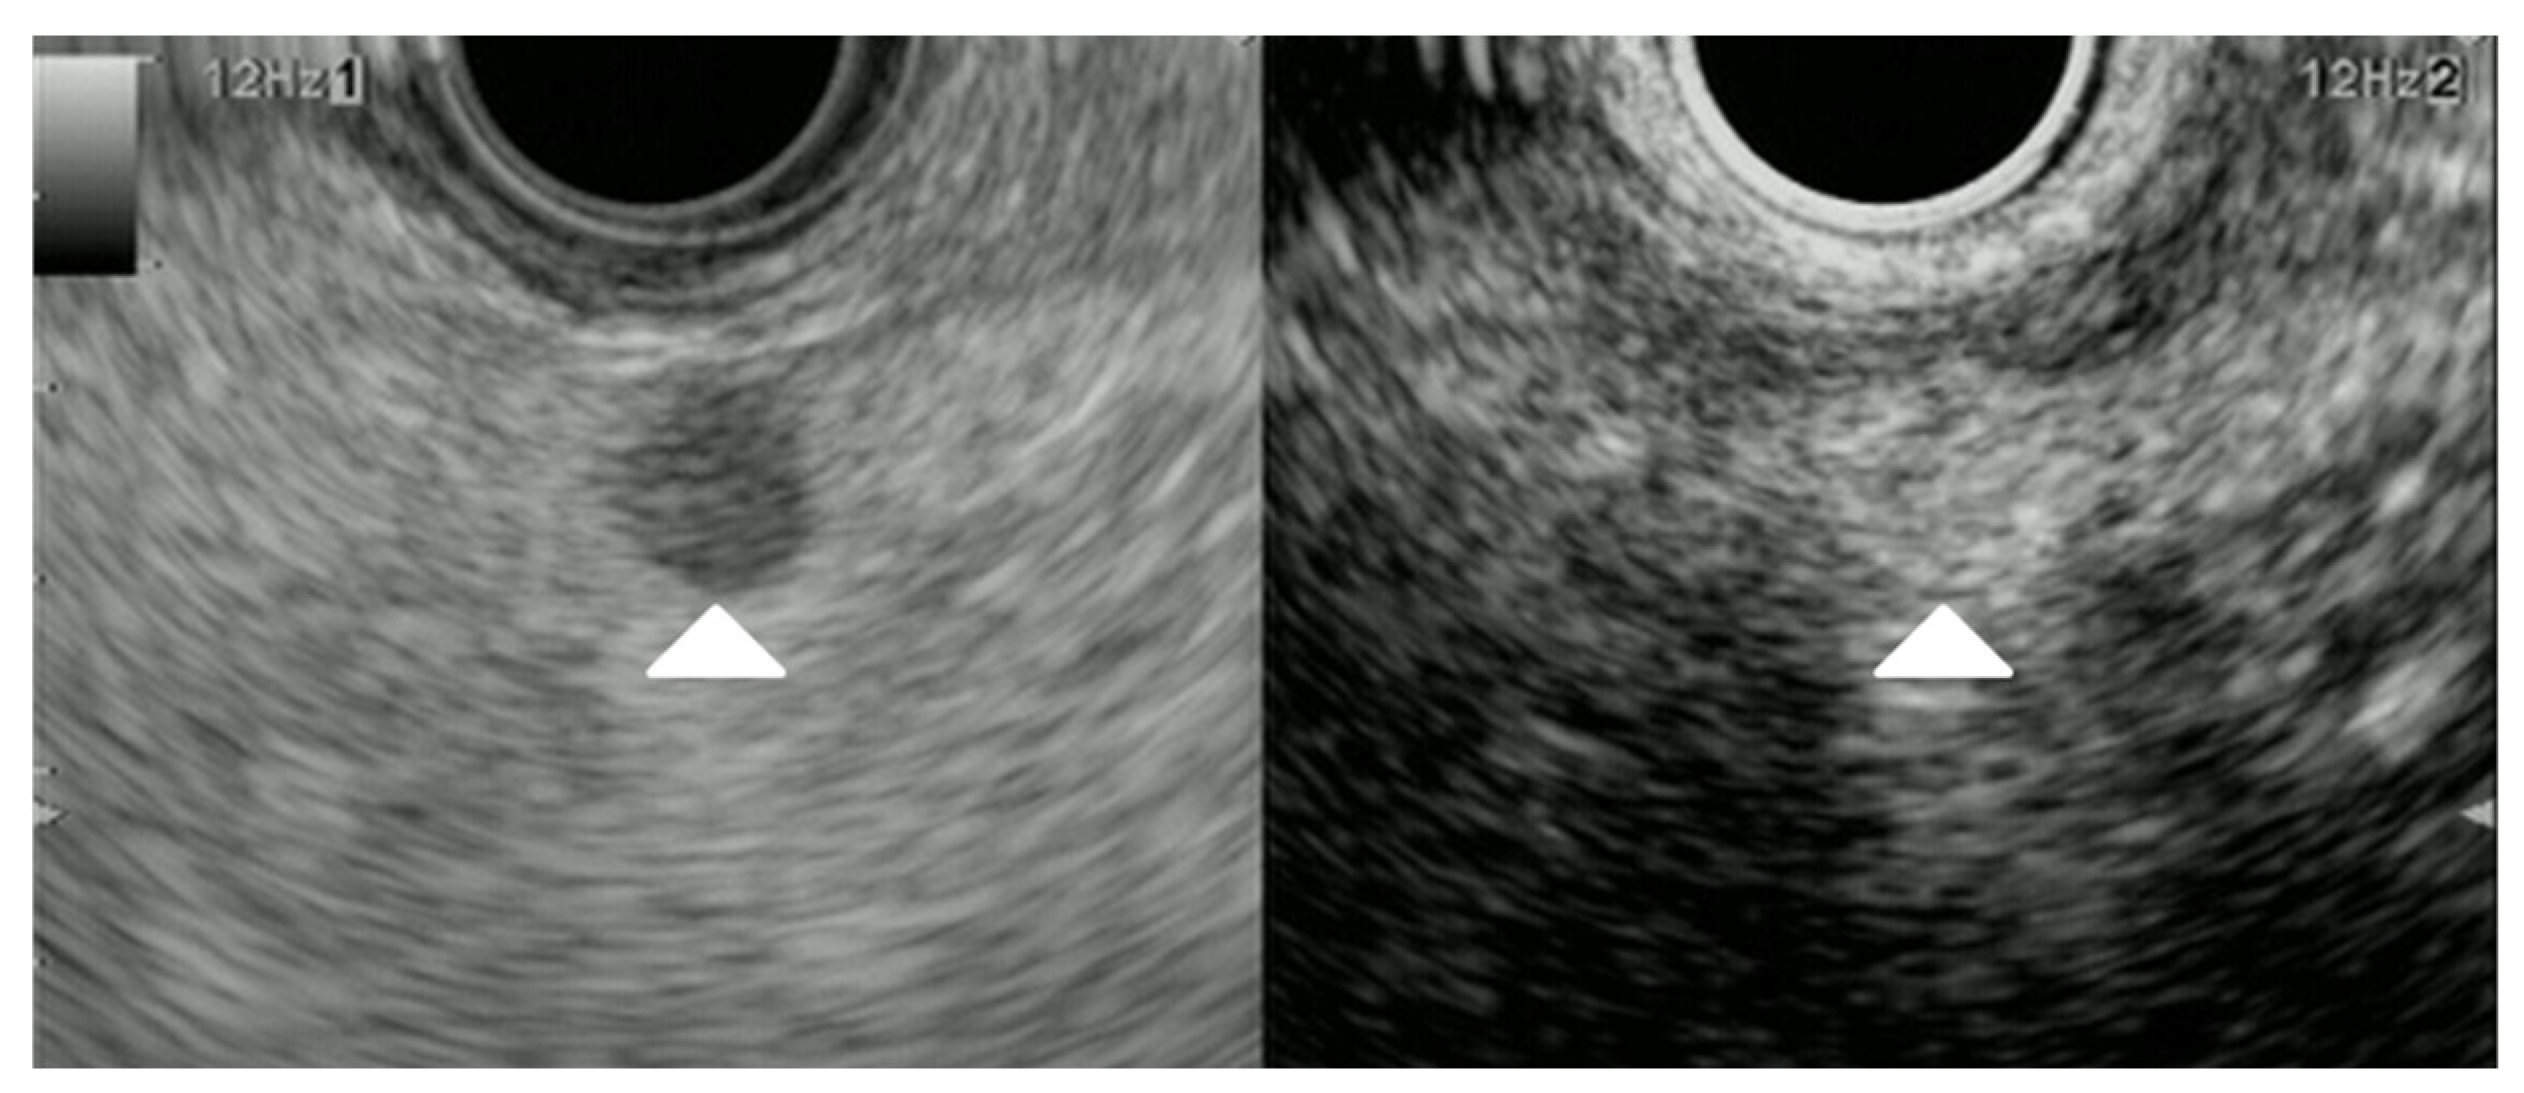

| Elastography (small lesions up to 15 mm) [67] | 41% softer or isoelastic, 59% stiffer compared to pancreatic parenchyma | 4% soft or isoelastic, 96% stiffer compared to pancreatic parenchyma | 64% soft or isoelastic, 36% stiffer compared to pancreatic parenchyma |